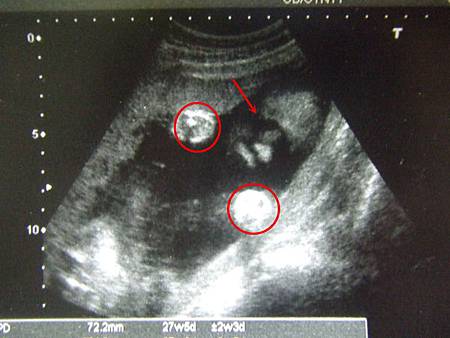

圖說:框起來的是兩隻手@28週 圖說:ㄧ個月前的搗蛋鬼